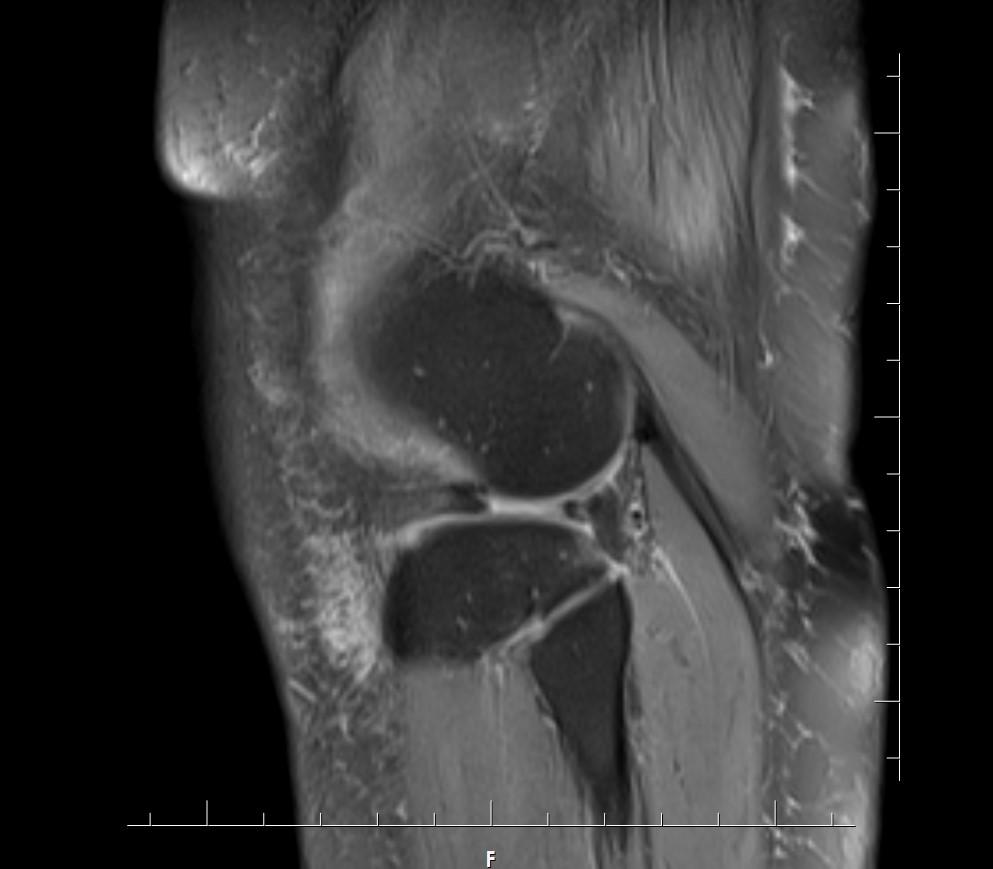

Answer: Bucket-handle tear of the lateral meniscus

Fat-suppressed images demonstrate a large displaced “handle” from the body of the lateral meniscus near the intercondylar notch.